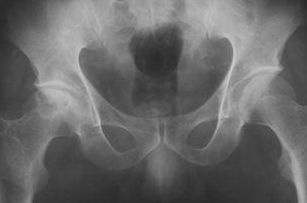

但最多不超過(guò)5次。穿刺注意事項:骶裂孔與珠網(wǎng)膜下腔終端的距離最長(cháng)約75mm,最短為19mm,平均約47mm,故穿刺針不要進(jìn)入骶管內過(guò)深,以免刺入珠網(wǎng)下腔引起不良后果。

骶管腔容積最小12ml,最大65ml,平均30ml,故注入藥液最大劑量不宜超過(guò)30ml。